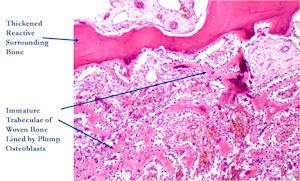

Microscopic Pathology

- Interlacing network of bone trabeculae in a loose fibrovascular stroma

- Prominent vessels

- Osteoblasts are plump, active, scattered mitotic figures

- Osteoblasts line up around periphery of trabeculae (Osteoblastic Rimming)

- Soft tissue component usually surrounded by shell of reactive bone or periosteum (Egg Shell Rim of Calcification)